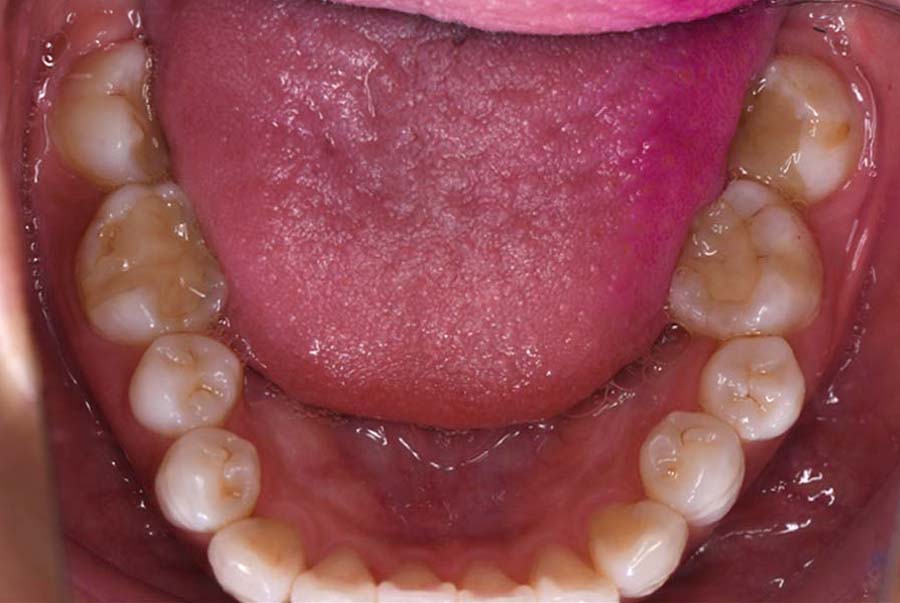

噛み合わせ治療の症例24

スプリント使用後、

補綴治療をした症例

基本情報

| 治療内容 | ①スプリントを装着 ②副子を装着 ③2024年4月 口腔内反映開始 ④副子を入れた状態の所まで咬合を挙上 (バイトアップ) ⑤2024年5月 上顎前歯部8本へ仮歯(TEK) を装着 |

初診日 2023年10月12日